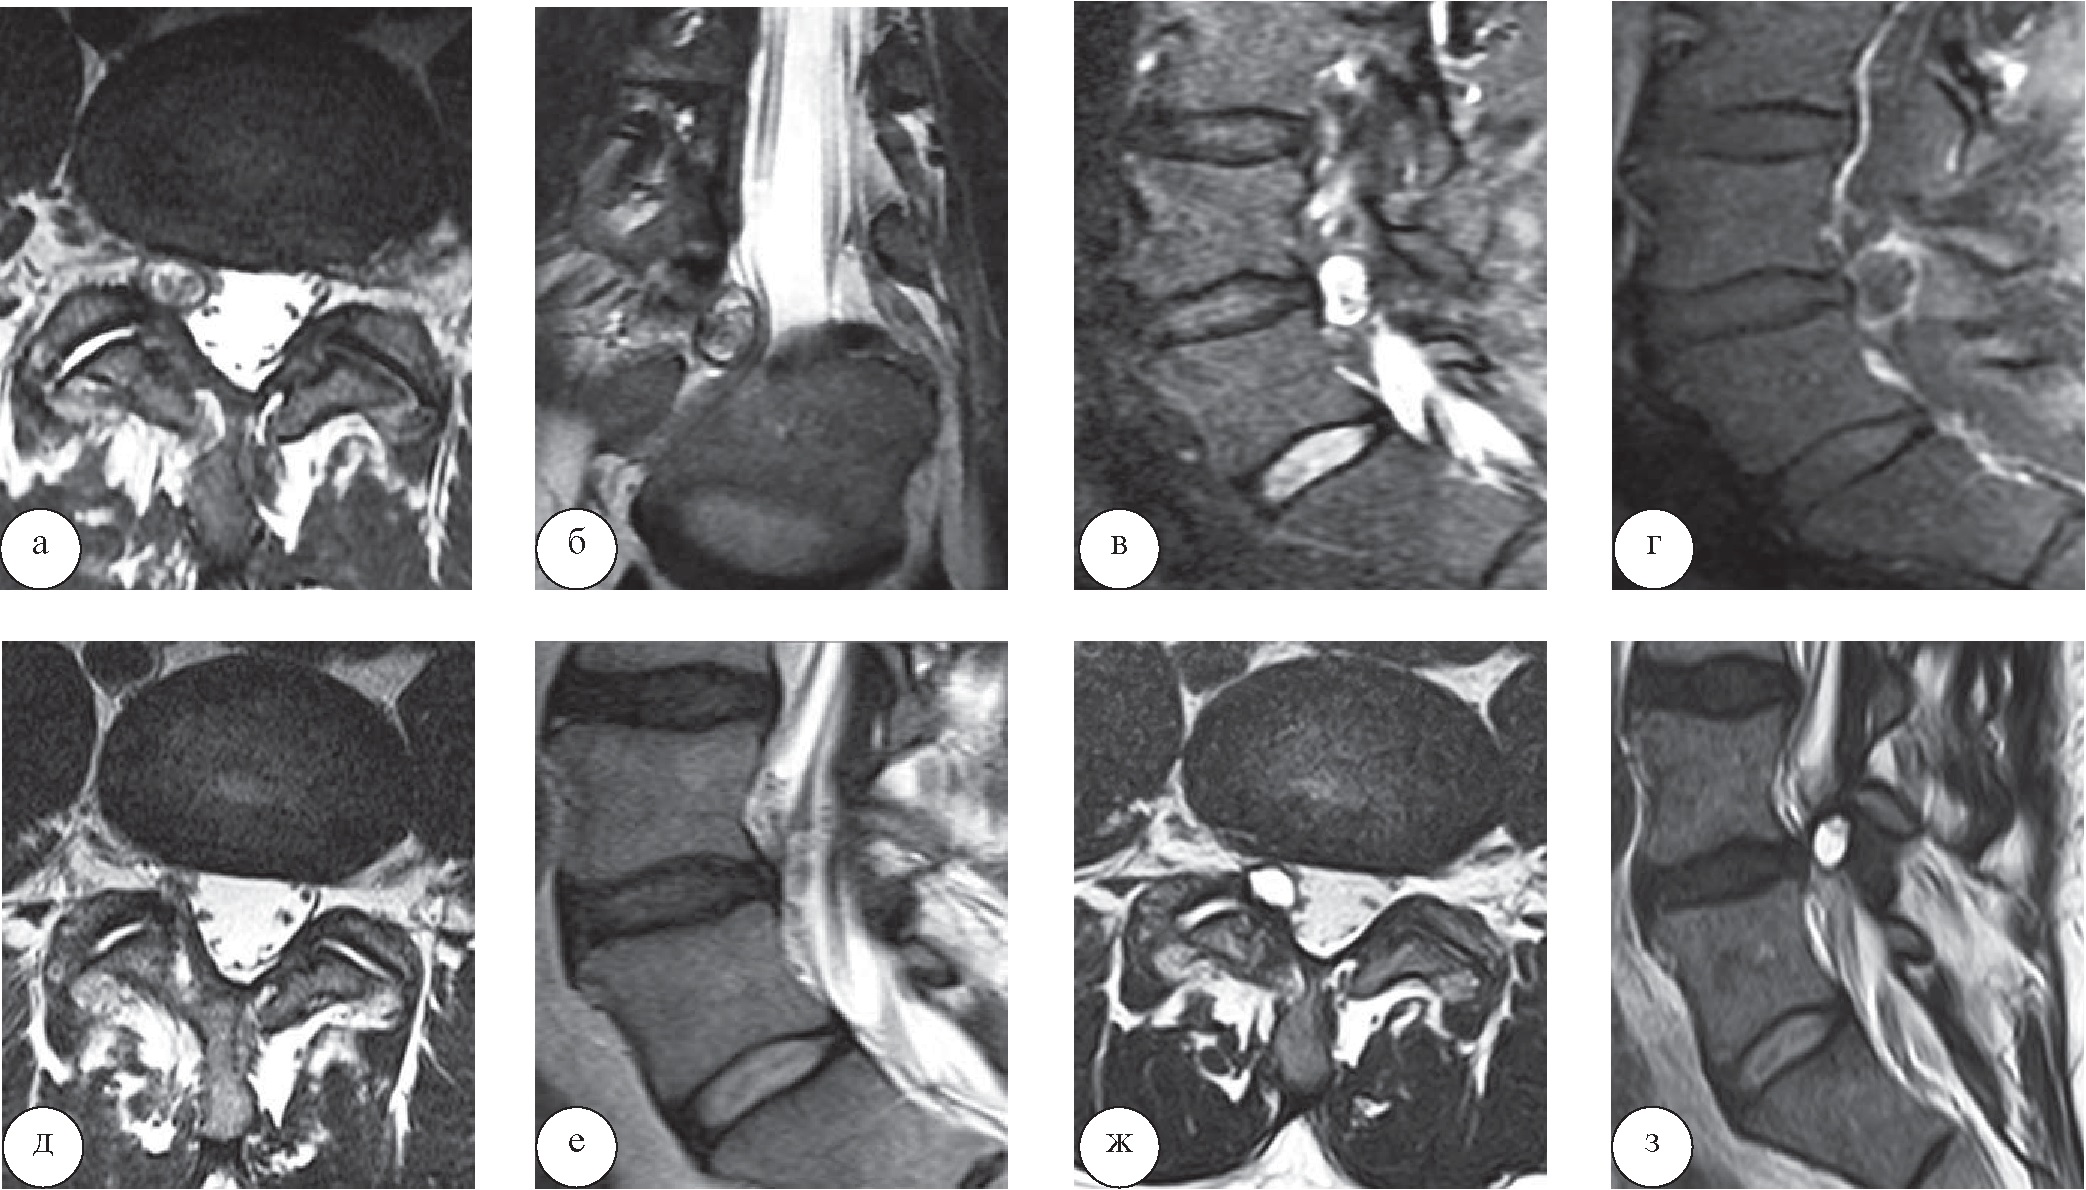

Периоперационных осложнений не отмечено. Средний койко-день при микрохирургическом лечении составил 10,4 суток, при перкутанных эндоскопических операциях – 4,7 суток. У трех пациентов контрольные МРТ выявили повторное возникновение параартикулярных кист в зоне ранее проведенной операции (рис. 5).

Рис. 5. Рецидив параартикулярной кисты LIV–LV после перкутанной эндоскопической операции: а, б, в, г – дооперационные МРТ (а, б – сагиттальная и фронтальная МР-проекции (режимы Т2-ВИ), в, г – сагиттальные проекции (Т2-ВИ с жироподавлением и Т1-ВИ с контрастом); д, е – МРТ через сутки после операции (аксиальная и сагиттальная МР-проекции в режиме Т2-ВИ); ж, з – МРТ через 1 год после операции (аксиальная и сагиттальная МР-проекции в режиме Т2-ВИ)

Рецидивов у пациентов с дисковыми кистами не отмечено. К настоящему времени ни в одном из наблюдений (катамнез 6–12 месяцев) необходимости в повторных операциях не возникло. Этот факт, вероятно, обусловлен меньшими размерами параартикулярных кист в сравнении с картиной предоперационной МРТ и иным содержимым.

Наши крайне немногочисленные наблюдения в основном подтверждают результаты исследований большинства авторов работ по данной проблеме. Вместе с тем после эндоскопических вмешательств у двух из четырех пациентов при динамическом наблюдении через 12 и 16 месяцев выявлены признаки рецидива параартикулярных кист на фоне сохраняющихся МР-признаков артрита (см. рис. 5). Отсутствие неврологических проявлений у этих больных в настоящее время не исключает вероятности того, что в будущем им потребуются повторные операции. Рецидив после микрохирургического удаления ЭК возник всего в одном из семи случаев.